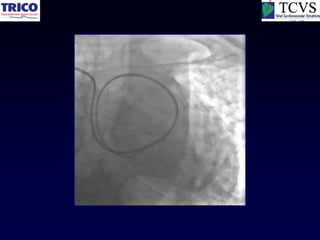

RCA CTO